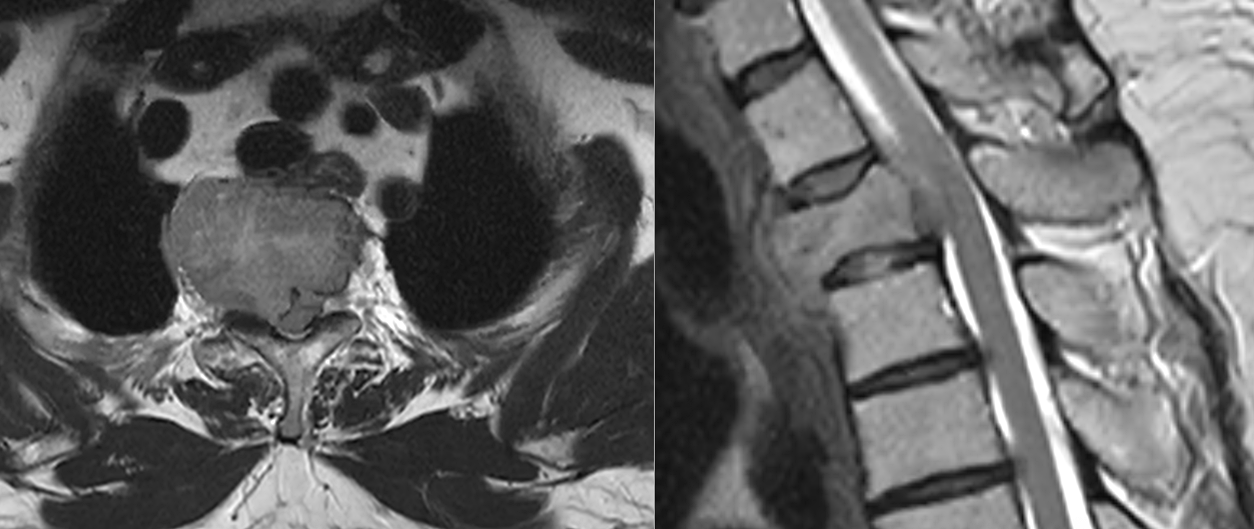

Localizarea tumorii influențează semnificativ tabloul clinic. Tumorile cervicale pot afecta rapid mobilitatea membrelor și respirația. Cele toracice pot evolua mai lent, dar pot produce compresii medulare severe. Tumorile lombare afectează frecvent nervii responsabili de mișcarea și sensibilitatea membrelor inferioare.

Diagnosticul tumorilor spinale osoase se bazează pe imagistică de înaltă performanță. Rezonanța magnetică este investigația principală, deoarece oferă informații detaliate despre os, măduvă și nervi. Tomografia computerizată este utilă pentru evaluarea distrugerii osoase.

În multe cazuri, este necesară o biopsie pentru a stabili cu certitudine natura tumorii. Acest pas este crucial înainte de inițierea tratamentului.